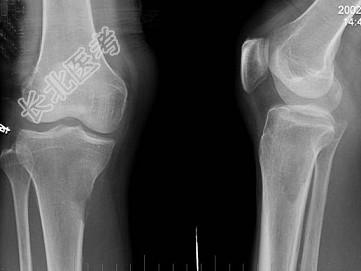

- 单项选择题男,59岁, 右小腿近端疼痛1年,活动障碍半年, 有前列腺癌病史,请结合所提供图像, 选择最佳答案 ( )

C、右胫骨骨转移